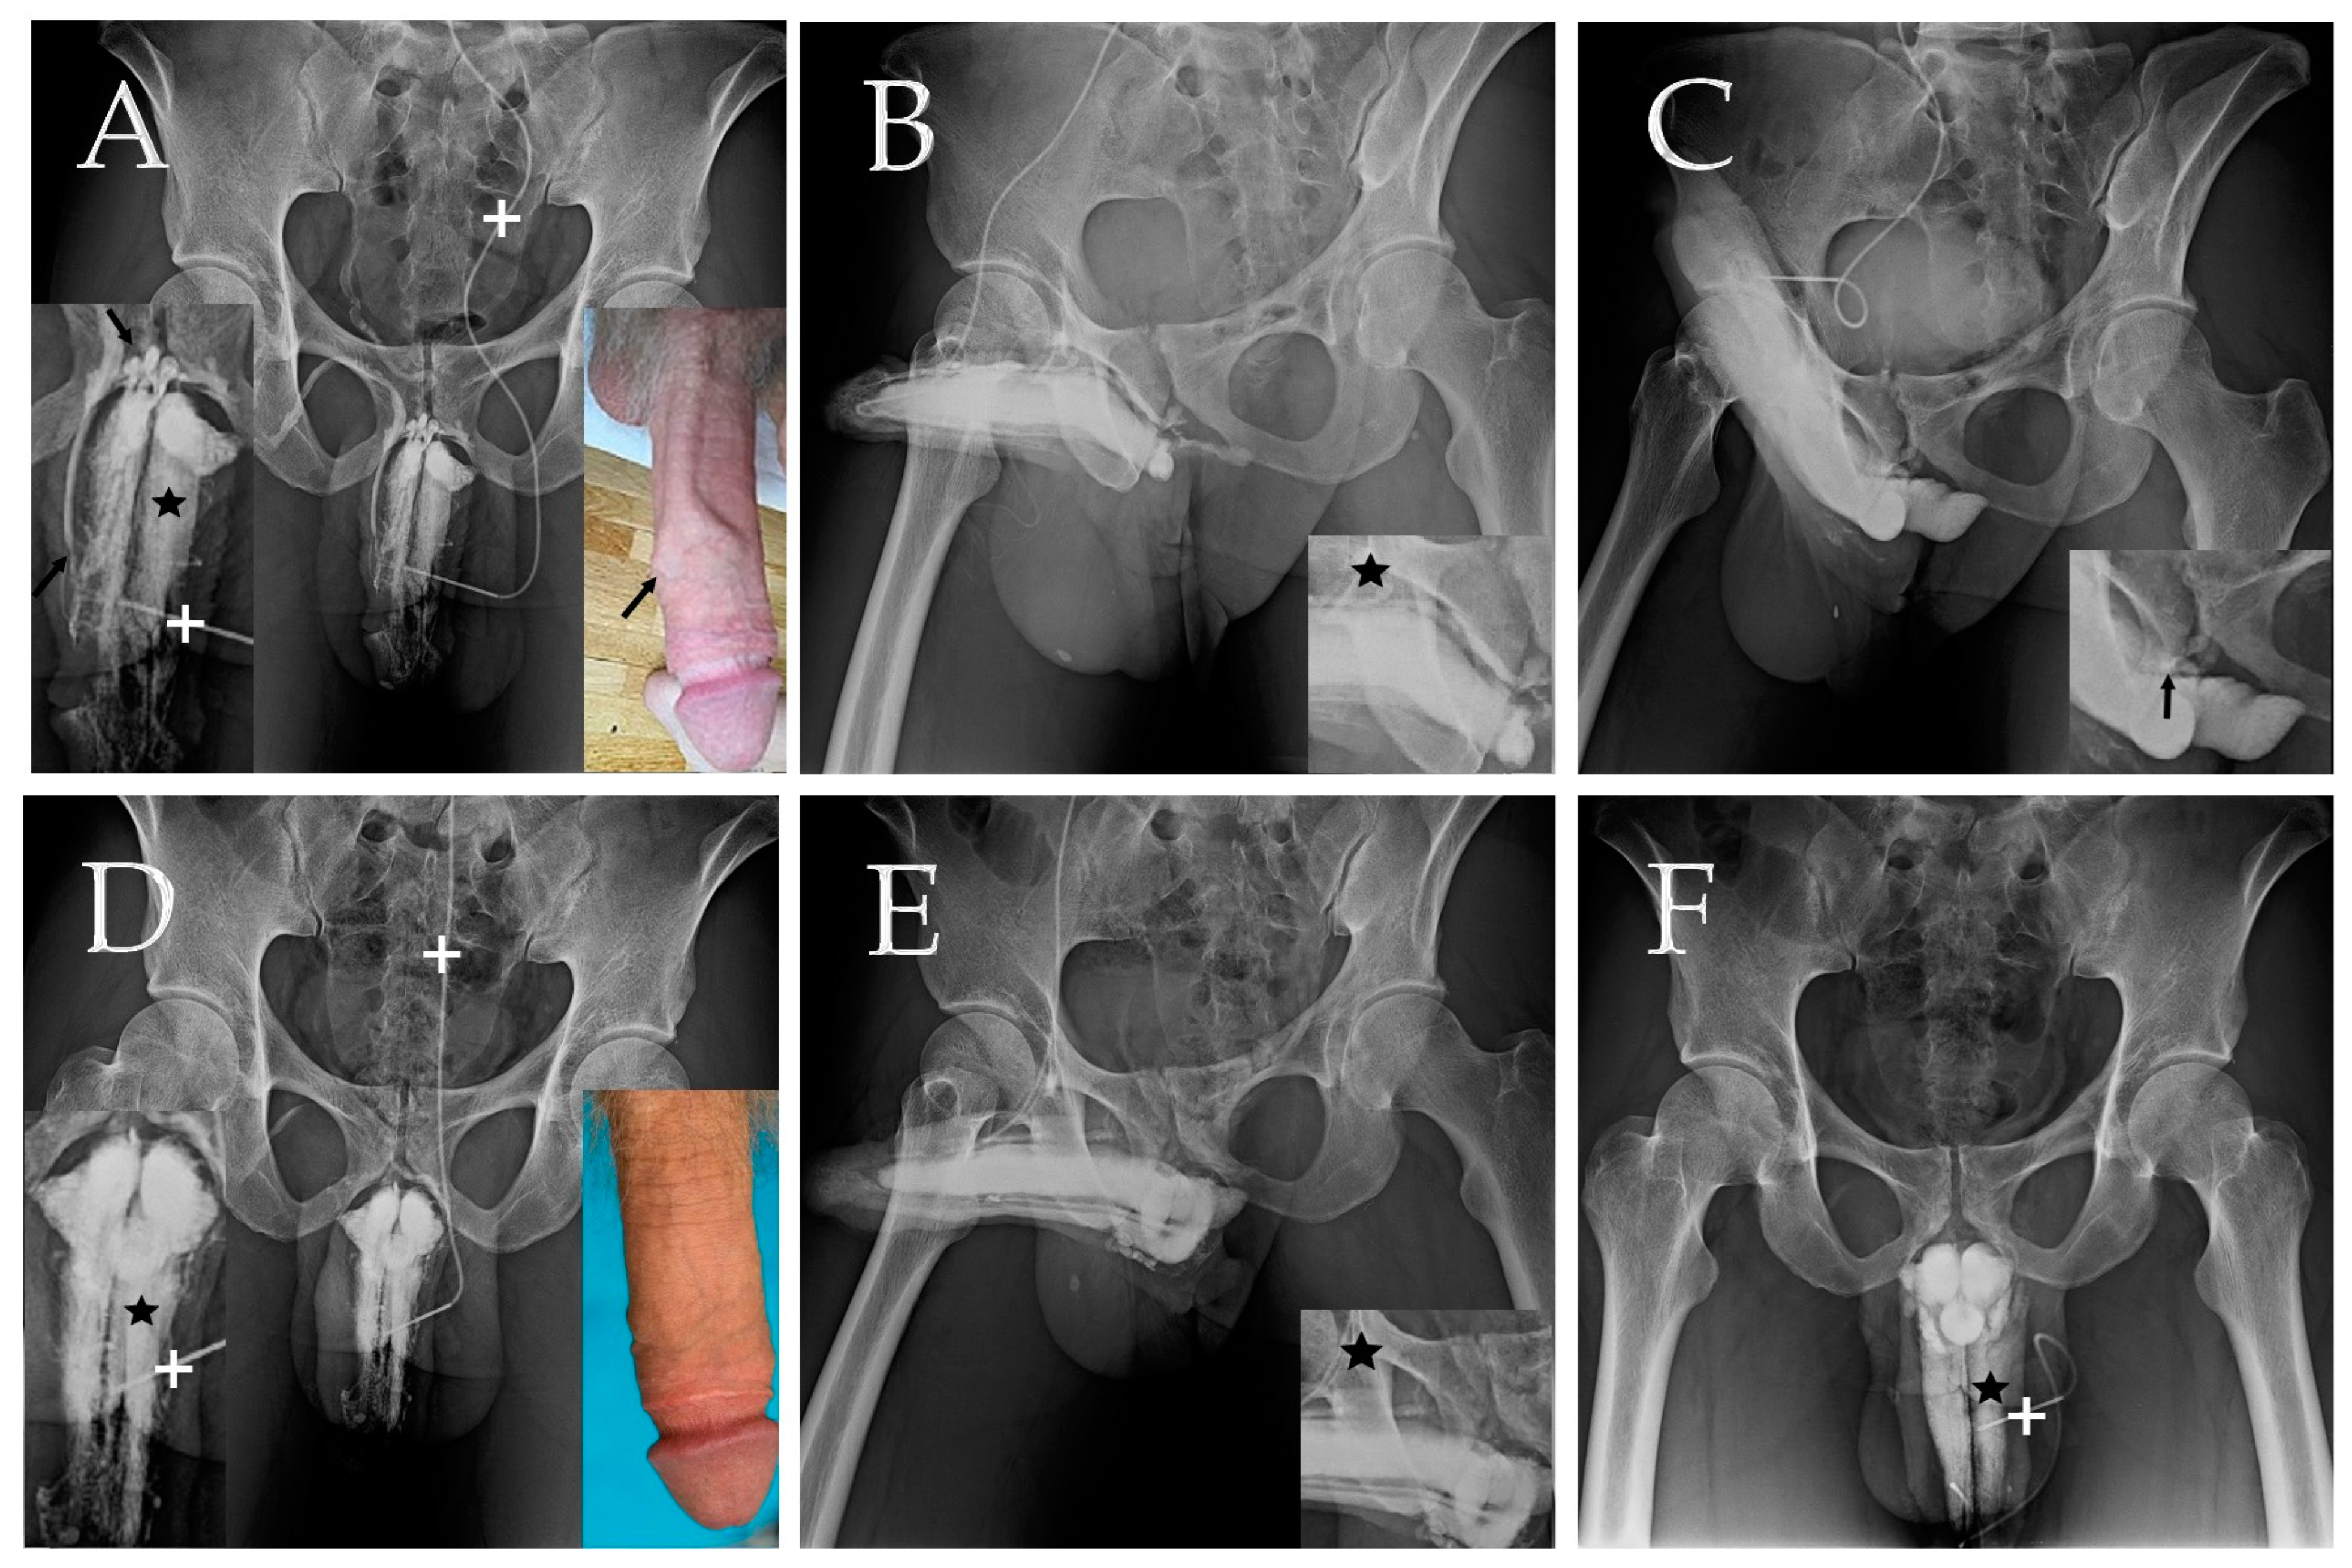

- Hsu, G.L.; Hill, J.W.; Chen, H.S.; Huang, S.J. Novel pilot films providing a dispensable information in pharmaco-cavernosography. Transl. Androl. Urol. 2014, 4, 398–405. [Google Scholar]